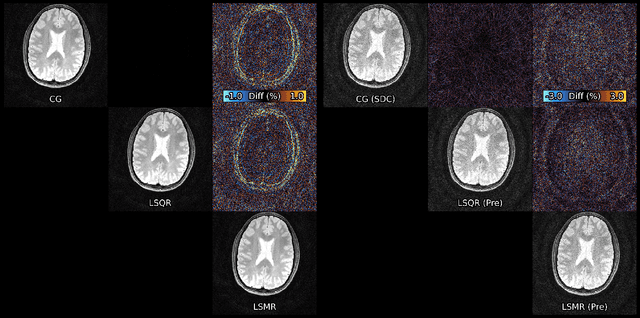

Figure 2 for Algorithms for Least-Squares Noncartesian MR Image Reconstruction